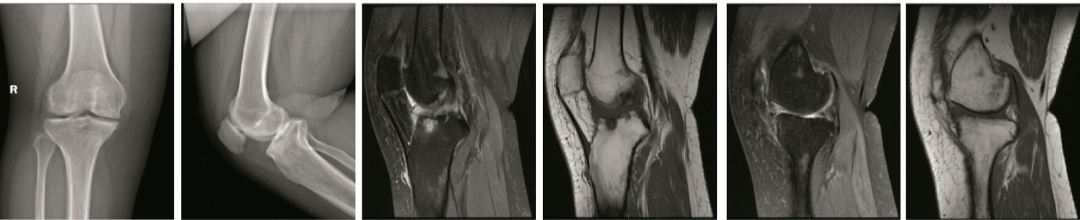

图3 术后1年的影像学资料